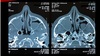

Dx

Sinusitis